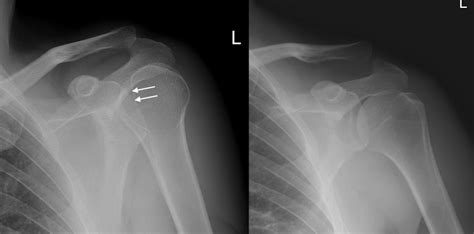

When the X-ray image is developed, the doctor will be looking for several key things. First and foremost, they want to see if the head of the humerus is indeed out of its socket. A normal shoulder X-ray will show the head of the humerus sitting snugly within the glenoid fossa. If it’s dislocated, the humerus will be displaced, often sitting in front of or below the socket. Secondly, they’ll be on the lookout for fractures. Fractures can occur in the humerus itself, the glenoid, or even the clavicle (collarbone), which is closely connected to the shoulder joint. The X-ray can reveal the type and severity of these fractures, which is vital information for planning treatment. Lastly, the X-ray can sometimes show other issues, such as pre-existing conditions like arthritis or bone spurs, which might influence the management of the dislocation. So, it’s a really comprehensive look inside your shoulder!

The primary goal of an X-ray in this scenario is to confirm whether a dislocation has occurred. A normal shoulder joint will show the head of the humerus (the ball) sitting neatly within the glenoid fossa (the socket). When a dislocation is present, the head of the humerus will be displaced, meaning it has popped out of the socket. The X-ray will clearly show this displacement. There are different types of shoulder dislocations, most commonly anterior (where the humerus moves forward) and posterior (where the humerus moves backward). The X-ray will help identify the direction of the dislocation, which is important for guiding treatment. It’s like having a map that shows exactly where the ball has rolled off the track. This visual confirmation is crucial for accurate diagnosis and planning the reduction (putting the shoulder back in place).

Detecting Fractures

As we touched on earlier, X-rays are also essential for detecting any fractures that may have occurred along with the dislocation. The force that caused the shoulder to dislocate can sometimes lead to breaks in the bones around the joint. Fractures can occur in the humerus, the glenoid, or even the clavicle. These fractures can range from small chips to more significant breaks. Identifying these fractures is critical because they can significantly impact the treatment plan. For example, a simple dislocation might be treated with closed reduction (manipulating the shoulder back into place without surgery) and immobilization. However, if there’s a fracture, surgery might be necessary to stabilize the bones. The X-ray provides a detailed look at the bone structure, allowing the doctor to identify any fractures and assess their severity. Think of it as checking the foundation of a house – you want to make sure everything is structurally sound before proceeding.